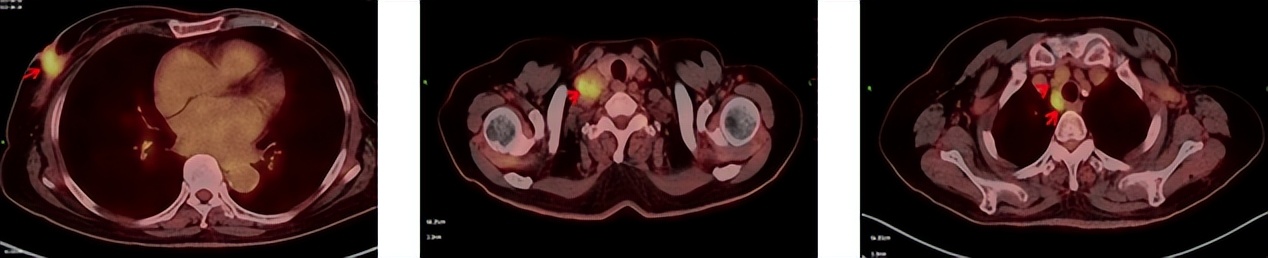

2023.6.26复查PET-CT

1.右乳外上象限乳腺癌病灶(22*16mm),对比2023-04-14 CT(26*24mm)较前缩小,FDG代谢活跃。右侧腋窝小淋巴结(5mm),较前稍缩小,代谢不活跃。右侧锁骨上区、上纵隔淋巴结转移瘤(24*18mm),现大小同前相仿,代谢活跃(SUV:6.7)。

2.现胃贲门部术后改变,术区未见明显异常活性灶。

3.左乳、左侧胶窝术后改变,未见明显异常活性灶。双肺小结节。考虑炎性结节可能,建议复查;双肺门及纵隔另反应性淋巴结。